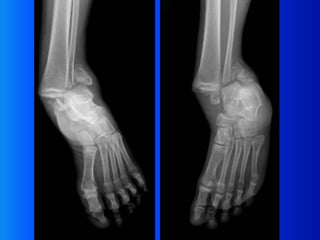

Ankle X-ray Interpretation | Ankle Fracture | Geeky Medics

Ankle fractures and how to interpret X-ray | PPTX

Ankle joint radiography | PPTX